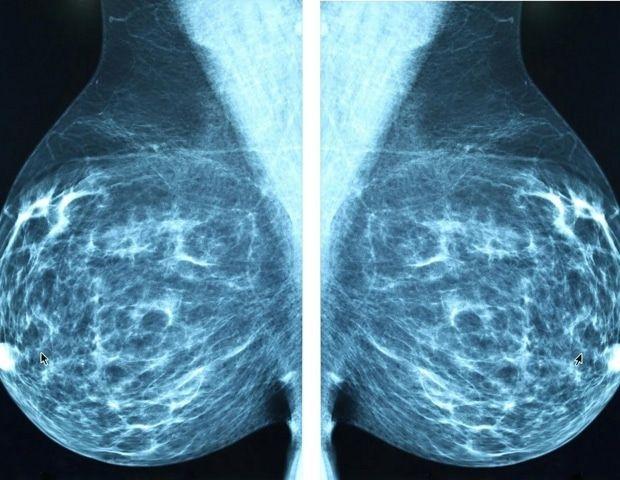

Radiological Society of North AmericaAug 19 2025 A hybrid reading strategy for screening mammography, developed by Dutch researchers and deployed retrospectively to more than 40,000 exams, reduced radiologist workload by 38% without changing recall or cancer detection rates. The study, which emphasizes AI confidence, was published today in Radiology, a journal of the Radiological Society of North America (RSNA). "Although the overall performance of state-of-the-art AI models is very high, AI sometimes makes mistakes," said Sarah D. Verboom, M.Sc., a doctoral candidate in the Department of Medical Imaging at Radboud University Medical Center in the Netherlands. "Identifying exams in which AI interpretation is unreliable is crucial to allow for and optimize use of AI models in breast cancer screening programs." The hybrid reading strategy involves using a combination of radiologist readers and a stand-alone AI interpretation of cases in which the AI model performs as well as, or better than, the radiologist. "We can achieve this performance level if the AI model provides not only an assessment of the probability of malignancy (PoM) for a case but also a rating of its certainty of that assessment," Verboom said. "Unfortunately, the PoM itself is not always a good predictor of certainty because deep neural networks tend to be overconfident in their predictions." To develop and evaluate a hybrid reading strategy, the researchers used a dataset of 41,469 screening mammography exams from 15,522 women (median age 59 years) with 332 screen-detected cancers and 34 interval cancers. The exams were performed between 2003 and 2018 in Utrecht, Netherlands, as part of the Dutch National Breast Cancer Screening Program. The dataset was divided at the patient level into two equal groups with identical cancer detection, recall and interval cancer rates. The first group was used to determine the optimal thresholds for the hybrid reading strategy, while the second group was used to evaluate the reading strategies. Of the uncertainty metrics evaluated by the researchers, the entropy of the mean PoM score of the most suspicious region produced a cancer detection rate of 6.6 per 1,000 cases and a recall rate of 23.7 per 1,000 cases, similar to rates of standard double-reading by radiologists. The final hybrid reading strategy involved AI evaluating every screening mammogram to produce two outputs: the PoM and an uncertainty estimate of that prediction. When AI determined the PoM was below the established threshold with certainty, the case was considered normal. When AI detected a PoM above the established threshold, women were recalled for further testing, but only when that prediction was deemed confident. Otherwise, the exam was double-read by radiologists. Although the majority of AI decisions were uncertain and deferred to a human reader, 38% were classified as certain and could be read solely by AI. Using the researchers' strategy reduced radiologist reading workload to 61.9% without changing recall (23.6‰ vs 23.9‰) or cancer detection (6.6‰ vs 6.7‰) rates, both of which are comparable to those of standard double-reading. When the AI model was certain, the area under the curve (AUC) was higher (0.96 vs 0.87). Its sensitivity nearly matched that of double radiologist reading (85.4% vs 88.9%). Younger women with dense breasts were more likely to have an uncertain AI score. "The key component of our study isn't necessarily that this is the best way to split the workload, but that it's helpful to have uncertainty quantification built into AI models," Verboom said. "I hope commercial products integrate this into their models, because I think it's a very useful metric." Verboom noted that if the study results occurred in clinical practice, the decision to recall 19% of women would be made by AI without the intervention of a radiologist. "Several studies have shown that women participating in breast cancer screening programs have positive attitudes about the use of AI," she said. "However, most women prefer their mammogram to be read by at least one radiologist." She said it may be more acceptable for radiologists to review exams deemed uncertain by AI, as well as AI recall cases. "The use of AI with uncertainty quantification can be a possible solution for workforce shortages and could help build trust in the implementation of AI," Verboom said. Verboom said further research, ideally a prospective trial, is needed to determine how the workload reduction achieved by the hybrid reading strategy could decrease radiologist reading time. "I think in the future, we could get to a point where a portion of women are sent home without ever having a radiologist look at their mammogram because AI will determine that their exam is normal," she said. "We're not there yet, but I think we could get there with this uncertainty metric and quality control." This study is part of the aiREAD project, which is financed by the Dutch Research Council, Dutch Cancer Society and Health Holland. Radiological Society of North America Journal reference: Verboom, S. D., et al. (2025) AI Should Read Mammograms Only When Confident: A Hybrid Breast Cancer Screening Reading Strategy. Radiology. doi.org/10.1148/radiol.242594.